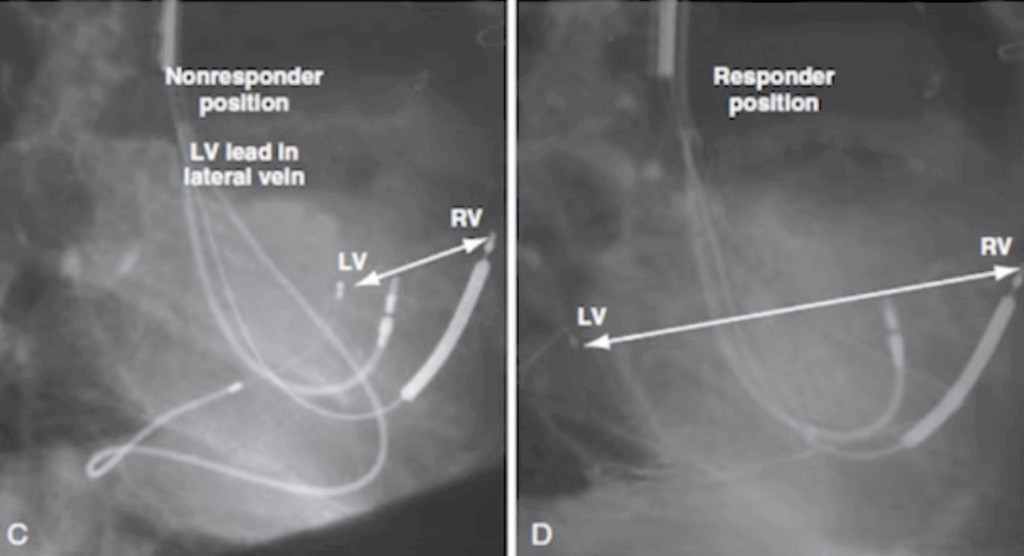

Here, the LV lead is well positioned. In the right-sided lateral view, you can clearly see that the LV lead is positioned far from the RV lead.

Look at the difference on the left: a non-responder, where the RV and LV leads are positioned side by side. You can already appreciate this during the procedure in the LAO view.

On the right, a good responder, with the LV lead re-positioned far from the RV lead.